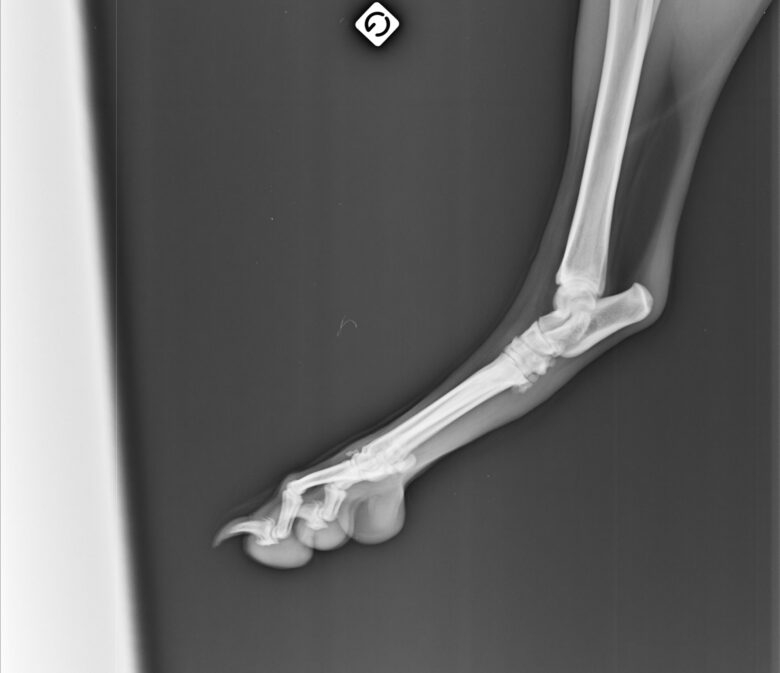

Nous avons choisi de faire une radio et c’est là que nous avons découvert l’impensable : Helly est atteinte d’une dysplasie très importante ainsi que d’arthrose et de becs de perroquet – les vertèbres se soudent entre elles et réduisent drastiquement la mobilité – à de multiples endroits.

L’intervention dure 30 à 40 minutes avec une sédation légère – ils n’intubent pas le chien a priori sauf exception – et le vétérinaire va venir déposer avec une grosse aiguille les implants d’or sur les zones prédéfinies. Helly a reçu 32 implants au total sur les hanches, la colonne et les poignets. A la Yourte, ils ne rasent que les zones nécessaires contrairement à d’autres cliniques qui rasent intégralement les hanches du chien par exemple.

Lors du contrôle post-opératoire de juillet 2025, le spécialiste constatait une belle amélioration de la mobilité sur la colonne mais plus timide sur les hanches, la zone la plus touchée. Rappelons que les effets sont évolutifs et progressifs dans le temps et qu’à 3 mois de l’opération, c’était donc parfaitement normal. En décembre 2025, constatant toujours quelques raideurs du train arrière notamment avec la période et les sorties hivernales, nous avons opté pour le laser en complément des implants. Après la 4ème séances de laser en janvier, Helly est en forme et ne présente pas de boiterie en revenant des sorties. D’ailleurs nous n’en avons jamais eu de nouvelles après la fameuse sortie de ski de rando à fond les ballons à 6 ans. Elle peut toujoursavoir des raideurs à froid en rentrant d’une grosse sortie mais le lendemain tout va bien.